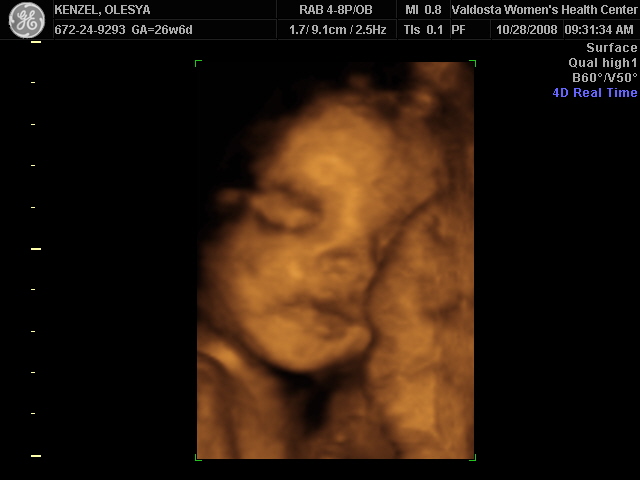

Ксюнь, а мы вообще не поняли. Она на всех фотках разная, да еще размытость такая. Пуповина то на носу болталась, то руками-ногами закрывалась. Главное что четкости нет совсем. Лоб у мужа тоже большой, а носы и губы зачастую на 3Д-4Д выходят разамазанно-пухло-приплюснутыми Поставлю для наглядности фотку моей средней-Джианки с 3Д УЗИ, там видно черты намного лучше и она на себя ту похожа сейчас, хотя родилась мне совсем на фото УЗИ не казалась похожей.

KENZEL,OLESYA_3.JPG [ 56.84 КБ | Просмотров: 1399 ]

Еще одна Джианнка:

KENZEL,OLESYA_5.JPG [ 60.02 КБ | Просмотров: 1484 ]